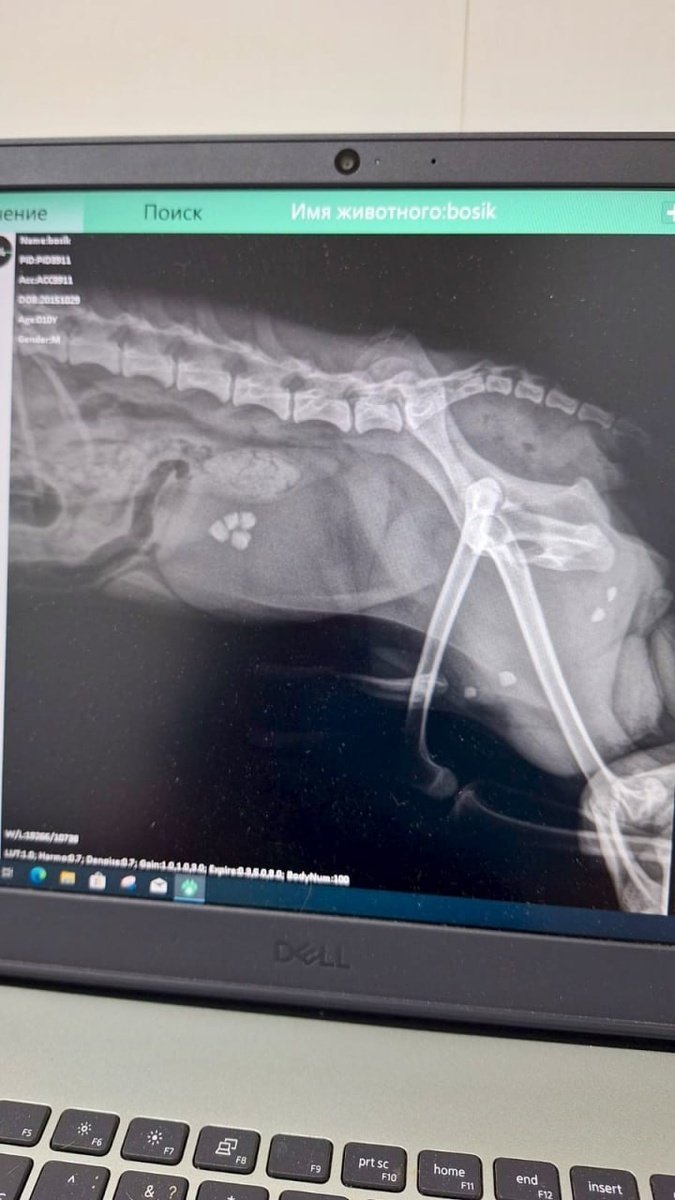

Это камни, удалённые из мочевого пузыря и мочеиспускательного канала йоркширского терьера 😯 😻Хирург - Юмашева Светлана Павловна 😻Уролог - Атаева Марина Владимировна

😻Хирург - Юмашева Светлана Павловна

😻Уролог - Атаева Марина Владимировна